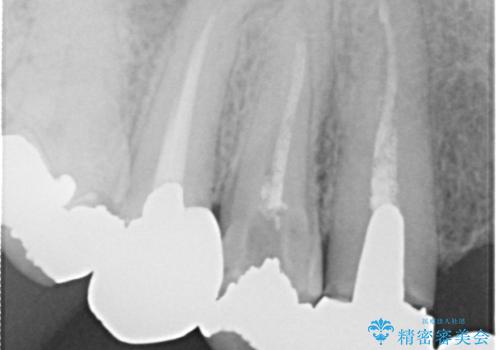

- 歯がない左側でものが咬めず、右側で咬むと歯が痛むので診て欲しいといらっしゃった方の症例です。

根尖病変が認められる歯は再根管治療を行い、歯根が破折していた左上4は抜歯しました。

インプラントは希望されなかったため、左側は1番から7番のロングスパンブリッジによる補綴を行いました。